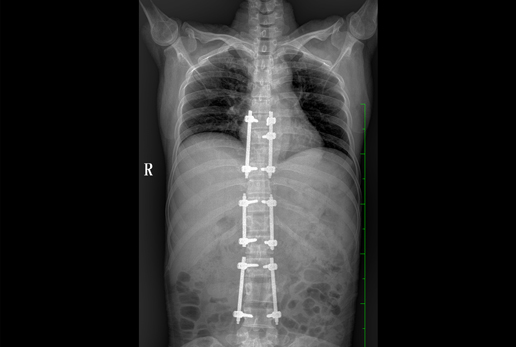

● 采用自主研發(fā)脈沖技術(shù),大尺寸動態(tài)平板,可實現(xiàn)動、靜態(tài)攝影模式無感切換,呈現(xiàn)更優(yōu)質(zhì)的圖像,為臨床醫(yī)生提供診斷依據(jù)。

● 集攝影、透視、造影等多功能為一體

● 核心優(yōu)勢: 大功率 動態(tài)平板 高清攝影 快速成像 透視造影 高清點片